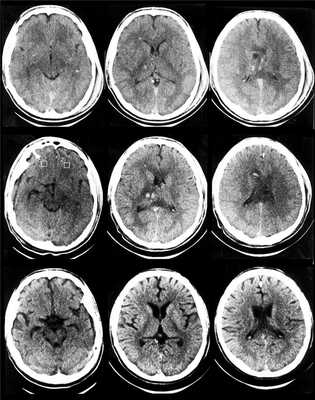

Анамнез: Юноша, 16 лет. Пешеход, сбит машиной. Поступил примерно через час после ДТП, кома. Разрыв селезенки, почки, ушибы легких, переломы костей таза, голени.

Описание исследования На первичной КТ: САК, внутрижелудочковое кровоизлияние, мелкий гиперденсный ушиб ствола по переднему контуру. Дифференцировка белого и серого вещества несколько смазана, конвексы дифференцируются.

Описание исследования на 2 сутки, постконтраст (после ОГК+ОБП с в/в контрастированием) Появление геморрагических очагов в полушариях мозга, следы САК и внутрижелудочкового кровоизлияния. Увеличилась смазанность дифференцировки серого и белого вещества. Появились мелкие геморрагические очаги в таламусе. Гиподенсный очаг с мозжечке слева расценен как, возможно, ишемический

Описание исследования 4-е сутки, постконтраст Постфактум отмечены гиподенсные очаги перивентрикулярно слева